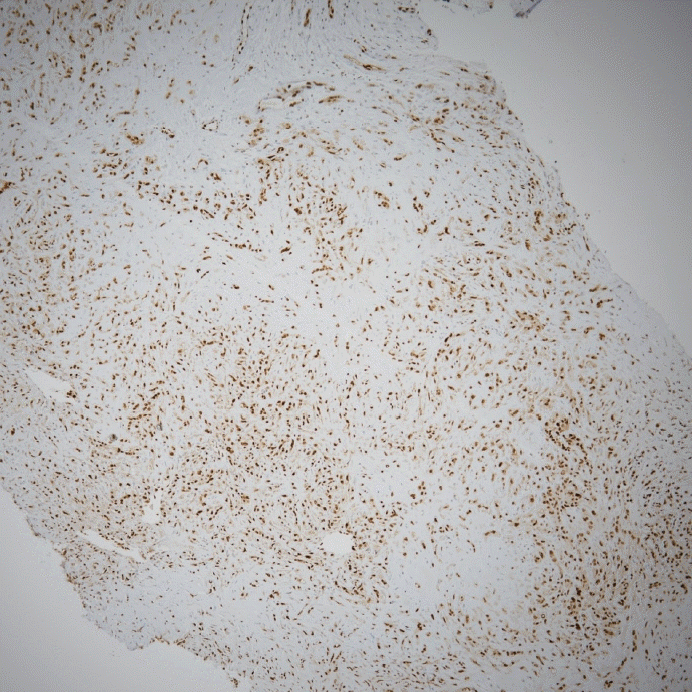

The sinus surgery confirmed fungal maxillary sinusitis. The final result of the incisional biopsy of the upper mediastinal mass was epithelioid hemangioendothelioma, and it was diagnosed as a malignant tumor. In a myxohyaline stroma, elongated cord-like arrangements of endothelial cells were embedded. The tumor cells had eosinophilic cytoplasm and vesicular, round or oval nuclei, and cytoplasmic vacuolization was observed in multiple cells (Fig. 3). On immunohistochemistry, the tumor cells were positive for CD34, an endothelial marker, and positive for ERG (E26 transformation specific [ETS]-related gene), a vascular marker (Fig. 4).

Immunohistochemical staining demonstrates diffuse positive for ETS(E26 transformation specific)-related gene (ERG), a vascular marker (ERG stain, ×100).